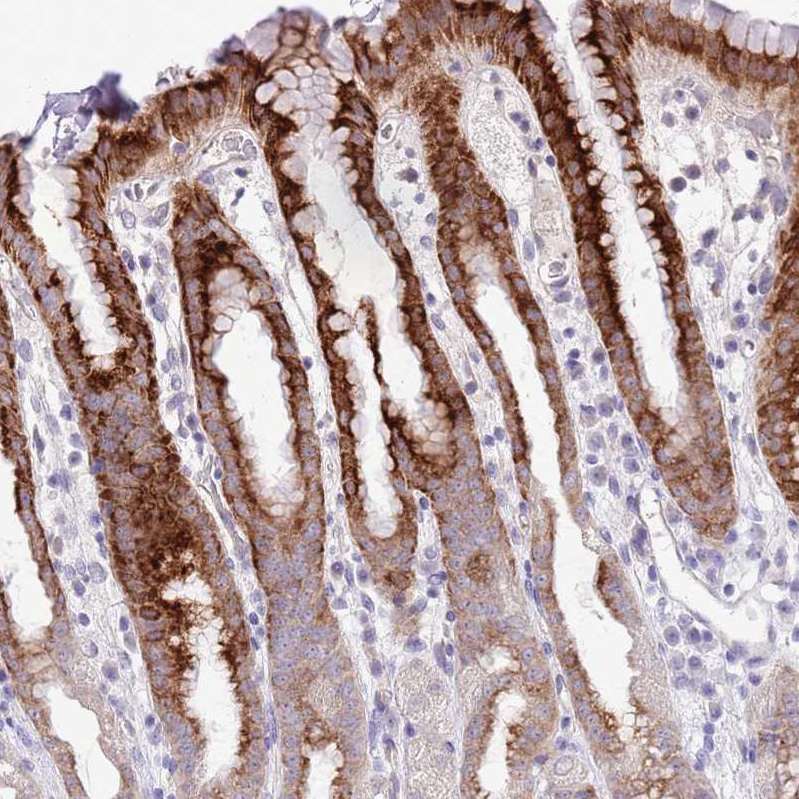

Immunohistochemical staining of human stomach shows strong cytoplasmic-membranous positivity in glandular cells.